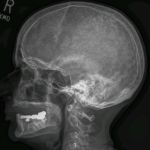

X-ray (Radiography) - Bone - RadiologyInfo.org

An x-ray (radiograph) is a noninvasive medical test that helps physicians diagnose and treat medical assist in the detection and diagnosis of bone cancer. locate foreign objects in soft tissues around or in bones. How should I prepare? ... Fetch Content